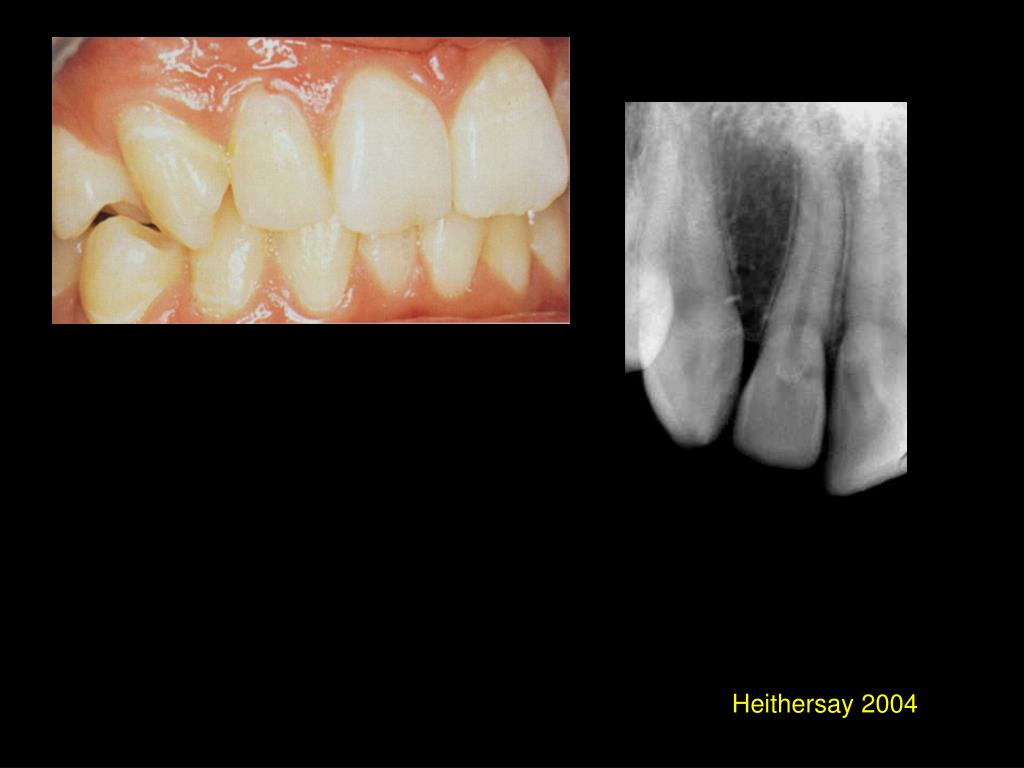

18. Heithersay 2004

19. Heithersay 2004

20. Heithersay 2004

21. Heithersay 2004